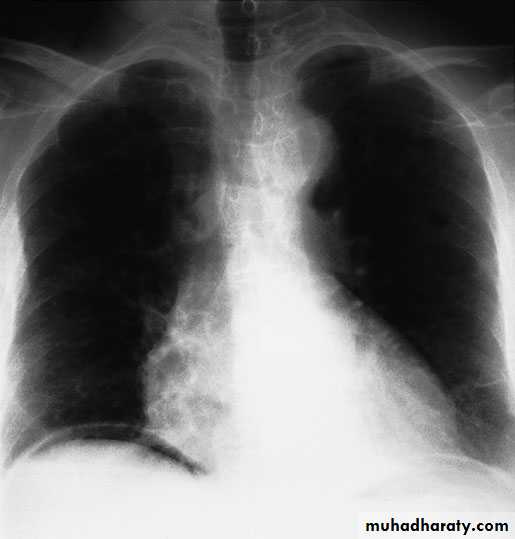

Imaging studies:

plain X ray of the abdomen

CXR in erect position.

U/S and/or CT Scan.